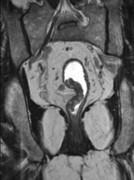

问题 男,70岁,下腹部腹胀、腹痛、排便困难,逐渐加重,MRI示直肠内不规则充盈缺损,请选择最佳诊断结果()

选项 A.直肠息肉 B.直肠癌 C.直肠间质瘤 D.直肠转移瘤 E.直肠淋巴瘤

答案 B